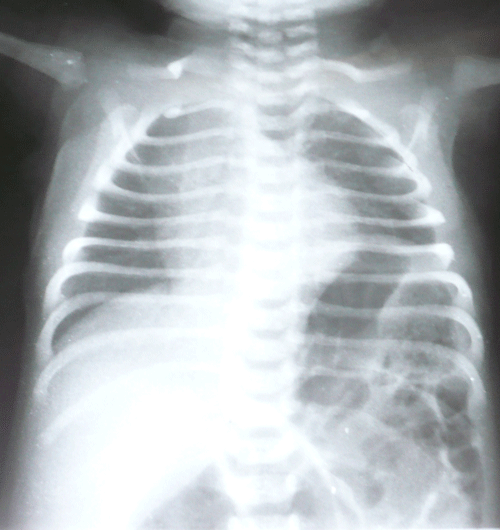

A 36-hour-old male neonate presented with imperforate anus and abdominal distension. There was no meconuria. Antenatal fetal anomaly scanning had not been done. Except for mild tachypnea (respiratory rate 60/min) physical examination of chest was nothing abnormal. Ultrasound of the abdomen did not reveal any anomaly. Invertogram (Fig. 1) showed a high variety imperforate anus. A sigmoid colostomy was performed. The colostomy started moving and patient was allowed orally the following day. The patient developed respiratory distress after starting feeds. A chest radiograph showed eventration of left hemidiaphragm (Fig. 2). A nasogastric tube inserted for gastric decompression alleviated the respiratory distress. The patient underwent plication of the diaphragm electively on 8th day of life. Postoperative recovery was uneventful. The patient is lost to follow-up.

Figure 2: Elevated left hemidiaphragm in the same patient. |